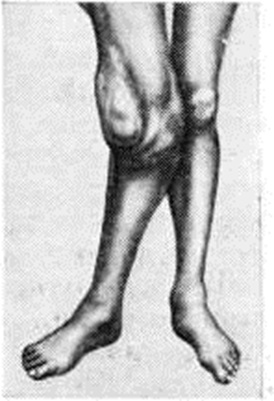

В заключительной стадии болезни атаксия и гипотония мышц усиливаются иногда столь резко, что больные не могут ходить; вследствие расстройства глубокой чувствительности исчезает представление о положении конечностей в пространстве, резко нарушается координация движений. Развиваются трофические расстройства: прободающие безболезненные трофические язвы стопы (malum perforans pedis), реже — ладоней, крыльев носа, мягкого неба и другие У 5—10% больных развиваются артропатии (смотри полный свод знаний), чаще коленного сустава (смотри полный свод знаний: рисунок 3), реже голеностопных, тазобедренных и локтевых. В редких случаях наблюдают артропатии позвоночника. Внутрисуставные и внесуставные патологический переломы костей при Спинная сухотка безболезненны; артропатии вызывают резкую деформацию суставов, однако пассивные движения и пальпация поражённого сустава боли не вызывают.

Течение Спинная сухотка весьма разнообразно. В связи с успехами современного комбинированного лечения ранних форм сифилиса (смотри полный свод знаний: Сифилис, лечение), а иногда и у лиц, не получавших лечения по поводу сифилиса, отмечают изменения в классической схеме течения Спинная сухотка: тяжёлые формы Спинная сухотка развиваются редко; течение заболевания стало более медленным и доброкачественным; часто выявляют атипичные и моносимптомные формы болезни. По данным современных исследователей, в настоящий, время из классических симптомов чаще всего отмечают зрачковые расстройства (миоз, анизокория), симптом Аргайлла Робертсона, явления атаксии (неустойчивость в позе Ромберга), нарушение сухожильных рефлексов и редко (в 6—8% наблюдений) — первичную атрофию зрительных нервов. Встречается прогрессирующая форма, когда постепенная потеря зрения заканчивается слепотой, и стационарная, при которой зрение падает до определенного предела и сохраняется на этом уровне длительное время. Первичная табетическая атрофия зрительных нервов может быть единственным проявлением Спинная сухотка Табетические артропатии возникают в настоящий, время у 1 — 2% больных Спинная сухотка, у 2—8% больных с табетической артропатией происходят патологический переломы (смотри полный свод знаний). Сохраняется типичный вариант клинические, картины с преимущественным поражением нижних конечностей (нижний табес); редко отмечается избирательное поражение сегментов конуса спинного мозга (анестезия в аногенитальной зоне, нарушение функции тазовых органов) или преимущественное поражение областей плечевого пояса и шеи (шейный табес). Больные Спинная сухотка остаются длительное время трудоспособными и до присоединения интенсивных стреляющих болей и висцеральных кризов редко обращаются за помощью к врачу.